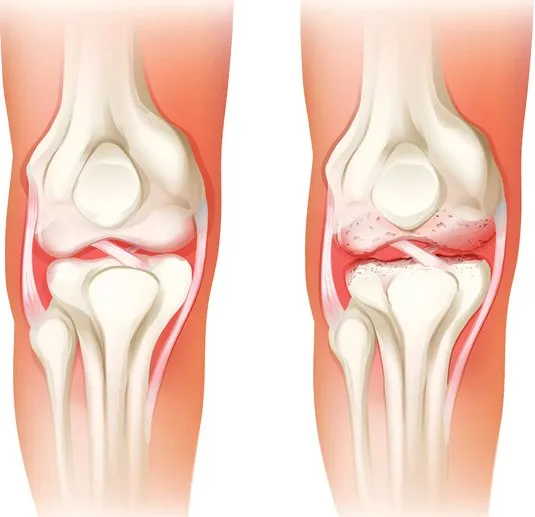

두 번째는 연골 손상

무릎 관절 사이에서 뼈와 뼈의 마찰을 줄여주는 부드러운 조직인 연골이 관련되어 있습니다. 나이 증가, 과체중, 관절염 등으로 인해 연골이 닳거나 소실되면, 뼈 사이의 직접적인 마찰로 인해 통증이 발생할 수 있으며, 이로 인해 움직임의 제한, 삐걱거리는 소리, 염증과 같은 증상이 나타날 수 있습니다.

이 상태의 치료는 체중 감량, 적절한 운동, 보조기 사용과 같은 자가 관리와 필요에 따라 진통제, 항염제, 보호주사, 관절경 수술 등의 의학적 치료를 포함할 수 있습니다.